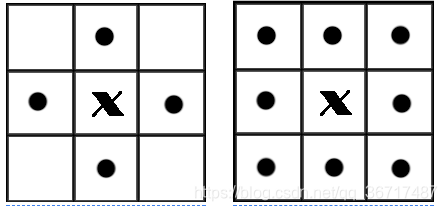

4.提取肺实质

在图像中,最小的单位是像素,每个像素周围有8个邻接像素,常见的邻接关系有2种:4邻接与8邻接。4邻接一共4个点,即上下左右,如下左图所示。8邻接的点一共有8个,包括了对角线位置的点,如下图所示。

如果像素点A与B邻接,我们称A与B连通,于是我们不加证明的有如下的结论: 如果A与B连通,B与C连通,则A与C连通。 在视觉上看来,彼此连通的点形成了一个区域,而不连通的点形成了不同的区域。这样的一个所有的点彼此连通点构成的集合,我们称为一个连通区域。 下面这符图中,如果考虑4邻接,则有3个连通区域;如果考虑8邻接,则有2个连通区域。